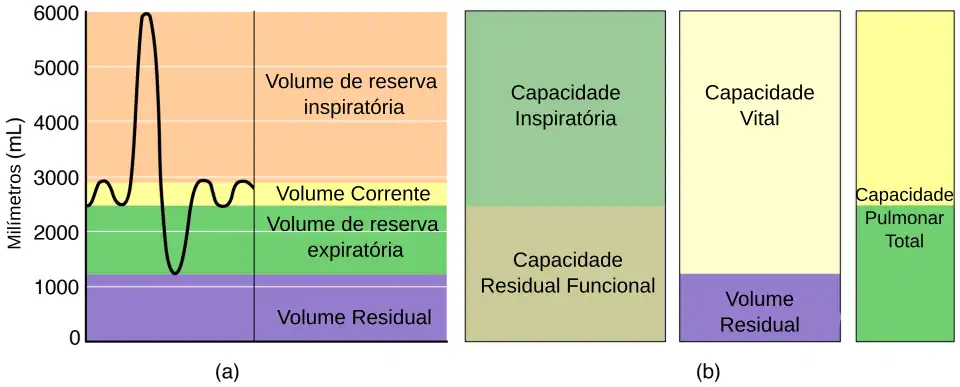

Volumes Pulmonares

Utilizando-se um espirômetro, é possível medir a variação do volume de ar nos pulmões em função do tempo, durante o processo respiratório. Normalmente, o volume máximo que o pulmão pode comportar, a chamada Capacidade Pulmonar Total (CPT) é de 6L, em adultos. No entanto, crianças e pessoas com doenças restritivas podem ter uma CPT diminuída, devido ao menor tamanho do pulmão e à diminuição da capacidade de expansão do pulmão, respectivamente.[14]

Todos os volumes pulmonares são subdivisões da CPT, no entanto, nem todos os volumes são recrutáveis para a respiração. O volume residual (VR) é o volume que "resta" no pulmão após uma expiração completa. Nesse sentido, VR representa o volume mínimo que o pulmão pode atingir fisiológicamente. Já os volumes de reserva, VRI (inspiratório) e VRE (expiratório) são volumes potenciais, ou seja, são volumes que podem ser recrutados em uma respiração forçada ou em exercício físico, mas que não são usados durante a respiração passiva.[9]

O volume corrente (VC) é o volume pulmonar recrutado durante um ciclo de respiração; o volume que é inspirado e expirado. Note que o Volume corrente é variável - o VC em repouso será menor que o VC em exercício, já que na atividade física ou respiração forçada há recrutamento dos volumes de reserva (VRI e VRE), aumentando a ventilação pulmonar e, portanto, aumentando o volume que é inspirado e expirado do pulmão em cada ciclo respiratório.[9]

Convenciona-se que as capacidades pulmonares são grupos de volumes pulmonares. Assim, a Capacidade Pulmonar Total (CPT) é simplesmente a soma de todos os volumes do pulmão. A Capacidade Inspiratória é a junção de VC com VRI, e a Capacidade Residual Funcional é a junção de VRI com VR. A Capacidade Vital (CV) considera os volumes que podem ser recrutados para a respiração - é o máximo de volume "útil" para a respiração.